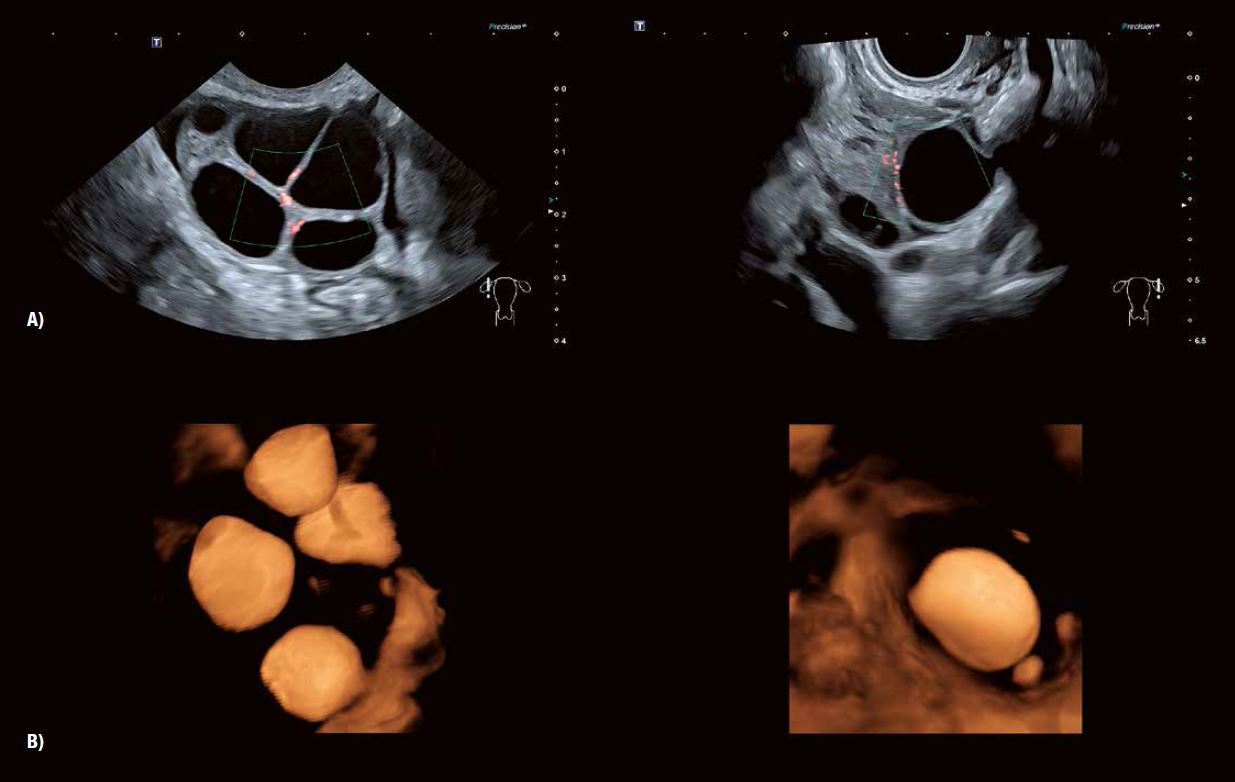

Рис. 1: Детальне зображення морфології яєчників  за допомогою 3D-реконструкції в сірій шкалі та візуалізації Shadow Glass відповідно. Розширена 3D-візуалізація візуалізує стійку, заповнену згустками лютеїнову кісту,  незрілі фолікули перед овуляцією, антральні фолікули,  а також атретичні фолікули та залишки фолікула, що пройшов овуляцію.

Рис. 3 A: 3D анатомічні площини показують типову мультифолікулярну природу структури фолікулів яєчників у віковій групі від раннього до середнього та пізнього підліткового віку.

Рис. 3 B демонструє зміну характеристик фолікулів та строми у жінок, наприклад, у віці від 25 до 39 років, особливо після пологів.

Рис. 3 C: Типовий вигляд у віковій групі 40 років.

Рис. 3 D: 2D- та 3D-зображення (Luminance) показують фолікули жінок у віці від 45 до 50 років. На відтвореному зображенні чітко видно контури фолікулів, що складаються з гранульозних та текальних клітинних шарів.

Ультразвукове дослідження та моніторинг росту фолікулів під час природного або пов'язаного з допоміжними репродуктивними технологіями циклу вже давно стали загальноприйнятою практикою. Прогрес у технології УЗД значно підвищив можливості оцінки дозрівання фолікулів та прогнозування початку овуляції (рис. 5). Сканування у високій роздільній здатності в сірій шкалі демонструє потовщення стінки фолікула внаслідок розвитку гранульозних та текальних клітин. Внутрішнє відшарування гранульозних клітин можна виявити в овуляційному фолікулі. 3D-візуалізація Fly Thru часто дозволяє розпізнати кумулюсну масу безпосередньо перед овуляцією (рис. 6). Розмір фолікула на початку овуляції може варіюватися від 1,8 до 3,0 см. Примітка: розмір фолікула сам по собі не завжди є показником його дозрівання.

Рис. 5 A: SMI визначає периферичний ангіогенез, пов'язаний із дозріванням фолікулів після стимуляції яєчників.

Рис. 5 B: 3D-візуалізація поверхні чітко окреслює фолікули на обох яєчниках.